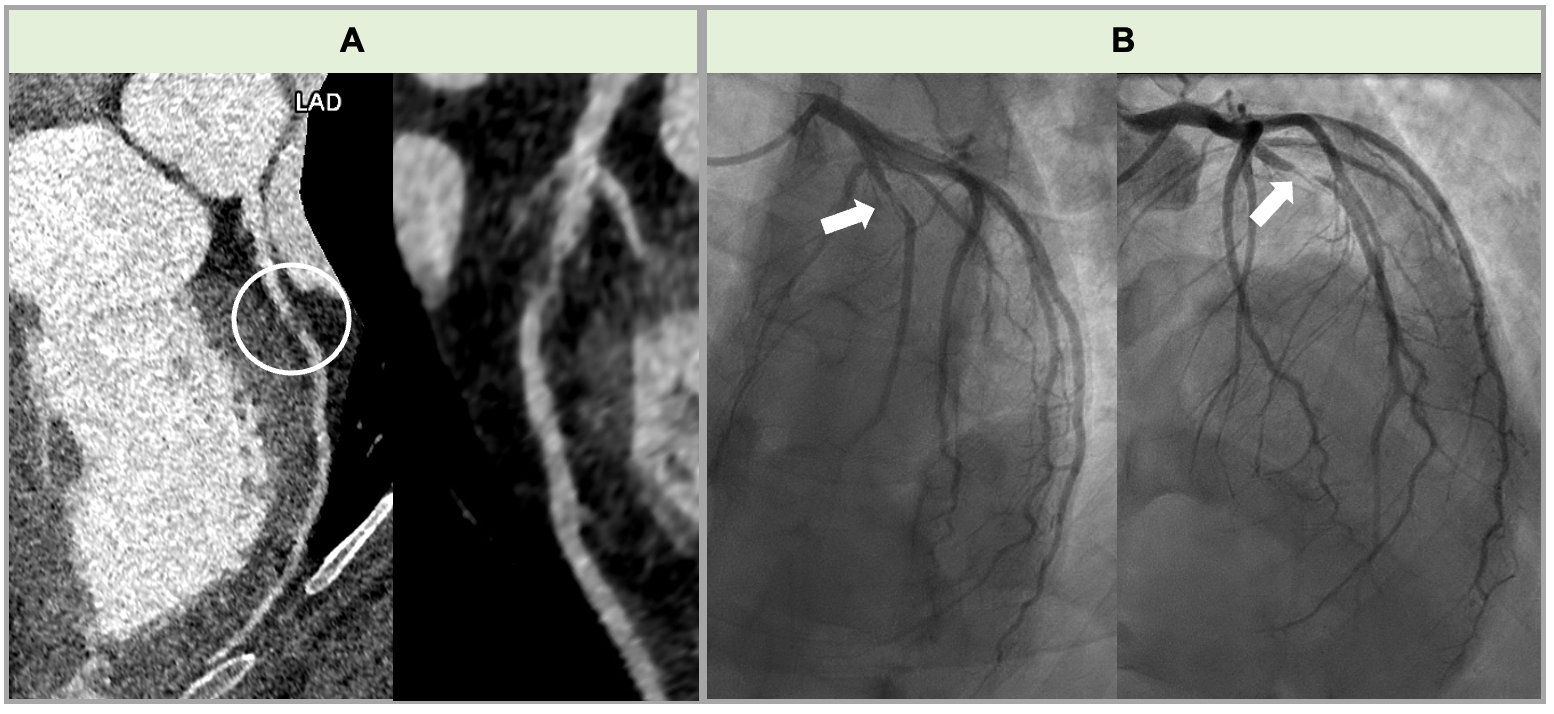

A 35-year-old G2P1 female with history of drug and tobacco use presented to the emergency department at 25 weeks of gestation with chest pain in the setting of a recent upper respiratory infection. Her vital signs and electrocardiogram (EKG) were normal; however, HS-troponin was elevated at 398 ng/L (normal <5.0 ng/L). An echocardiogram revealed a left ventricular ejection fraction (LVEF) of 55-60% and apical hypokinesis (Figure 1). The initial differential diagnosis included viral myocarditis (supported by elevated inflammatory markers), spontaneous coronary artery dissection (SCAD), and distal atherosclerotic coronary artery disease. Given her hemodynamic stability and preserved LVEF, the risk of invasive angiography outweighed the benefits. She was discharged with medical management and follow-up with maternal-fetal medicine and cardio-obstetric specialists.